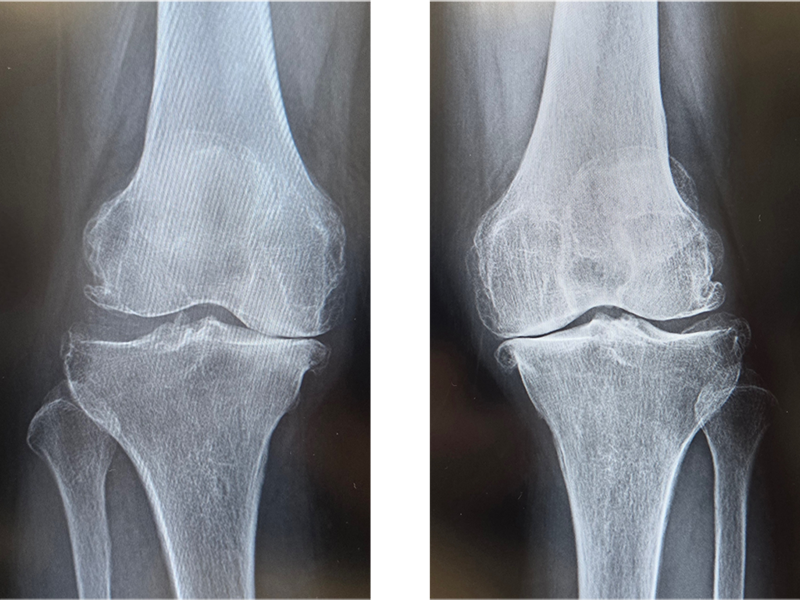

関節のなかで傷んだ部分だけ(多くは内側の半分だけ)を人工関節に置換します。メリットは手術の傷や削る骨の量が少ないため、術後の痛みも少なく、回復が早く、膝の曲がりもよいところです。耐久性も悪くありませんが、人工膝関節全置換術と比べると若干手技が難しく、適応をしっかり選ぶ必要があります。変形が比較的軽く、外側の軟骨や靭帯に異常がないなど、術前に専門医の診断を受けた上で、相談するようにしましょう。

UKAの術後

当院にて右人工膝関節全置換術(TKA)を施行。術前、歩行も困難でしたが、術後は杖歩行も安定し、良好な可動域も獲得。入院中に反対側の人工膝関節単顆置換術(UKA)も行い、十分なリハビリ後に退院となりました。